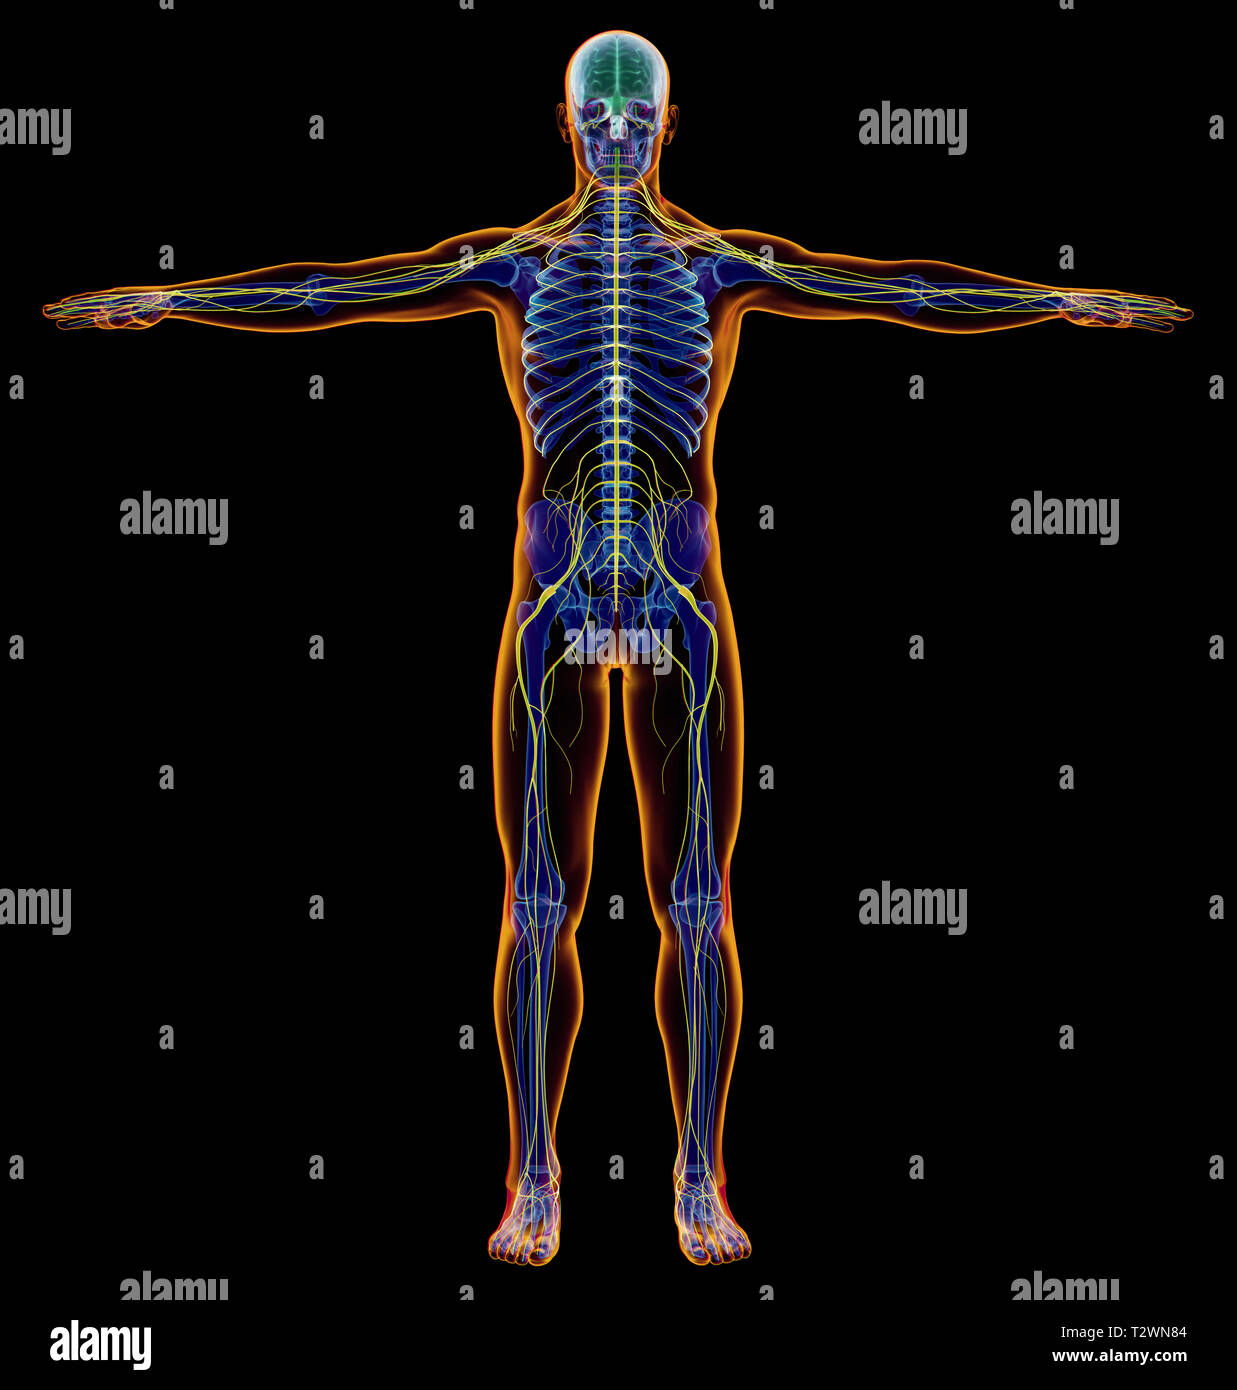

Anatomy of Human Organs in X-ray View Stock Illustration – Illustration …

The Human Body By X-rays On Blue Background. Stock Illustration …